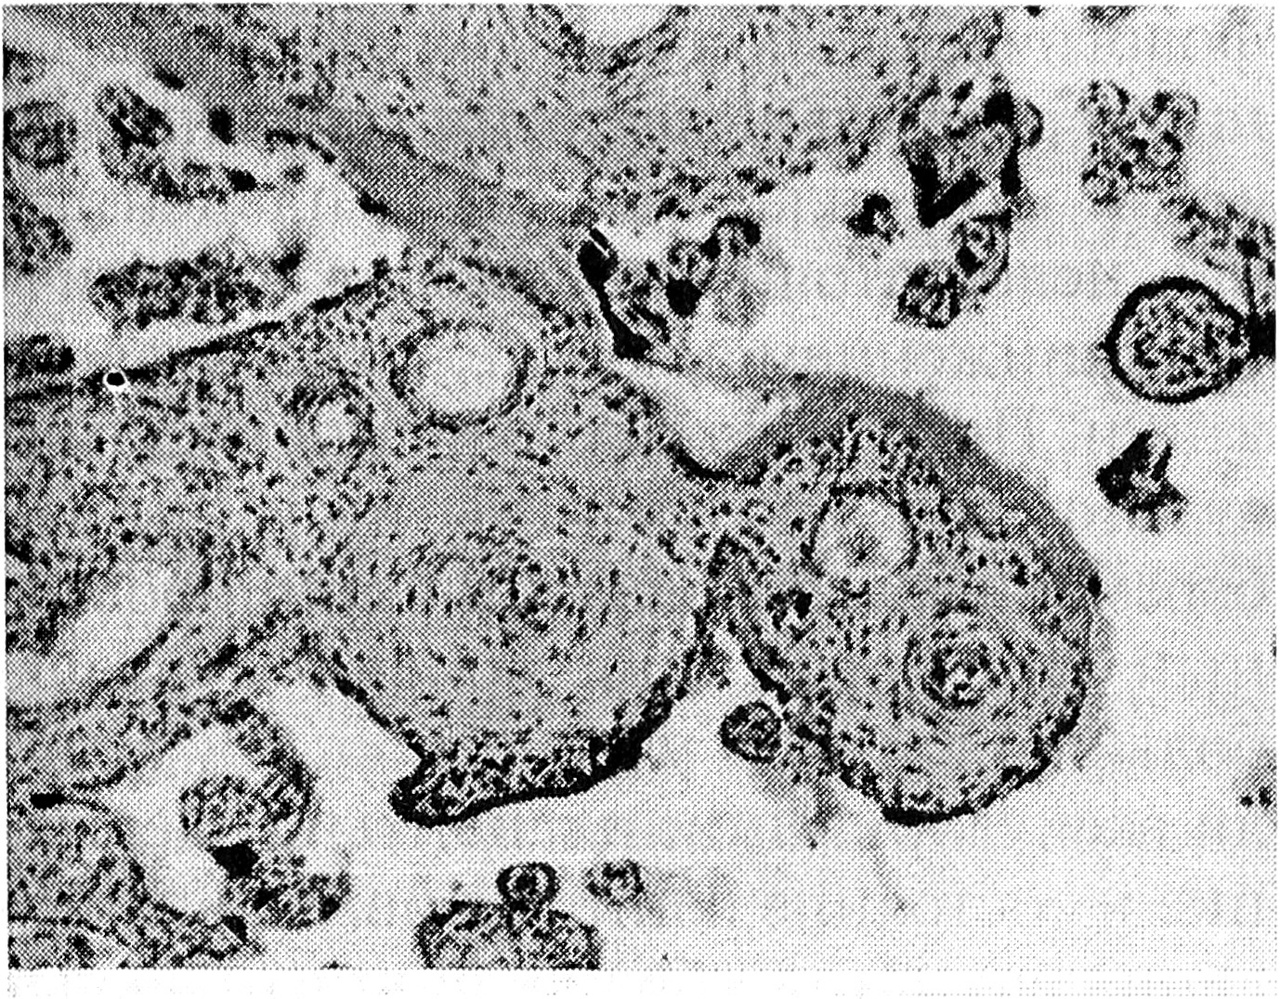

Рис. 2. Гиперпластический тип ворсин (с клеточной стромой и гиповаскуляризацией) при микоплазмозе, х 100

Наряду с общими для всех инфекций признаками нами обнаружены некоторые особенности в патоморфологической картине плаценты при каждом варианте инфицирования. В частности, при инфицировании микоплазмами БЛД характеризовался разной степенью воспалительной инфильтрации — от легкой до тяжелой, имел в 2/3 случаев' первый вариант развития, а в 1/3 — второй, причем первый вариант почти всегда протекал с отечным синдромом. В половине случаев это сопровождалось образованием крупных петрификатов в базальной пластинке и появлением известковых отложений в ворсинах (преимущественно в парабазальной зоне). Кровоизлияния были редкими. Обнаруживались гиперемия терминальных ворсин и слабая гиперплазия на них синцитиальных почек. Для пролиферативного варианта децидуита типичными были гиперплазия стромальных клеток в терминальных ворсинах, бедная их васкуляризация (рис. 2), гиперхромия ядер синцитиотрофобласта с образованием большого числа синцитиальных почек (в некоторых плацентах нарастало количество десквамированных почек в межворсинчатом пространстве), продуктивный васкулит и периваскулярный склероз в опорных ворсинах.